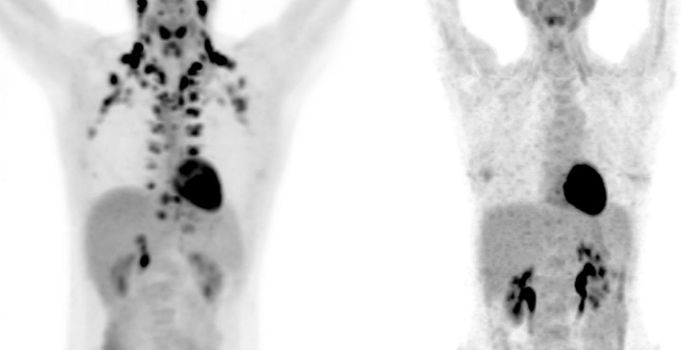

OCT 07, 2021CancerNeuroblastoma is a cancer of immature nerve cells found in various areas, including the adrenal glands, neck, chest ...